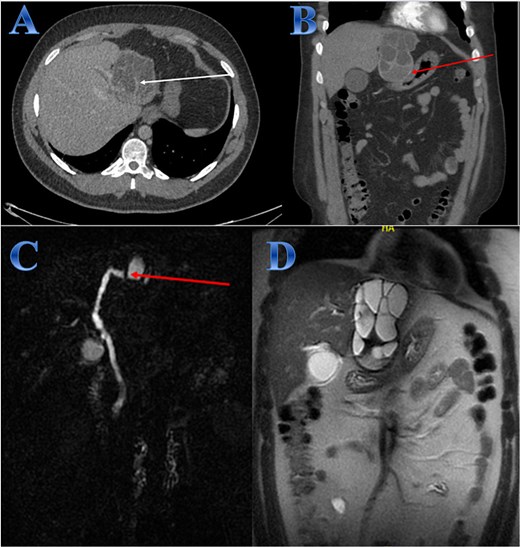

A 35-year-old lady with developed right upper quadrant abdominal pain suddenly. The laboratory tests showed a mild elevation of white blood cells and bilirubin levels. Abdominal US revealed a cystic structure extending from the right to the left hepatic lobes measuring 14 × 5 cm. CT with contrast revealed right hepatic intra-parenchymal cystic lesion with sub-capsular extension (Fig. 2).

Case 2. (A & B) Sagittal and axial CT cuts of the abdomen at venous phase showing right hepatic intra-parenchymal cystic lesion with subcapsular extension with no obvious post contrast enhancement. (C) MRI images showing right hepatic intra-parenchymal cystic lesion with subcapsular extension, proven to be sealed perforation. (D) The intraoperative finding after laparoscopic endocystectomy and the area of the cyst which was occupying the right hemi-liver under the ribs and reaching the diaphragm.

Laparoscopic endocystectomy was recommended. The liver was explored, and the cyst was isolated using gauze soaked in hypertonic saline. A suction device was used to puncture the cyst and aspirate the cyst fluid. Hypertonic saline was injected into the cyst (Fig. 2).